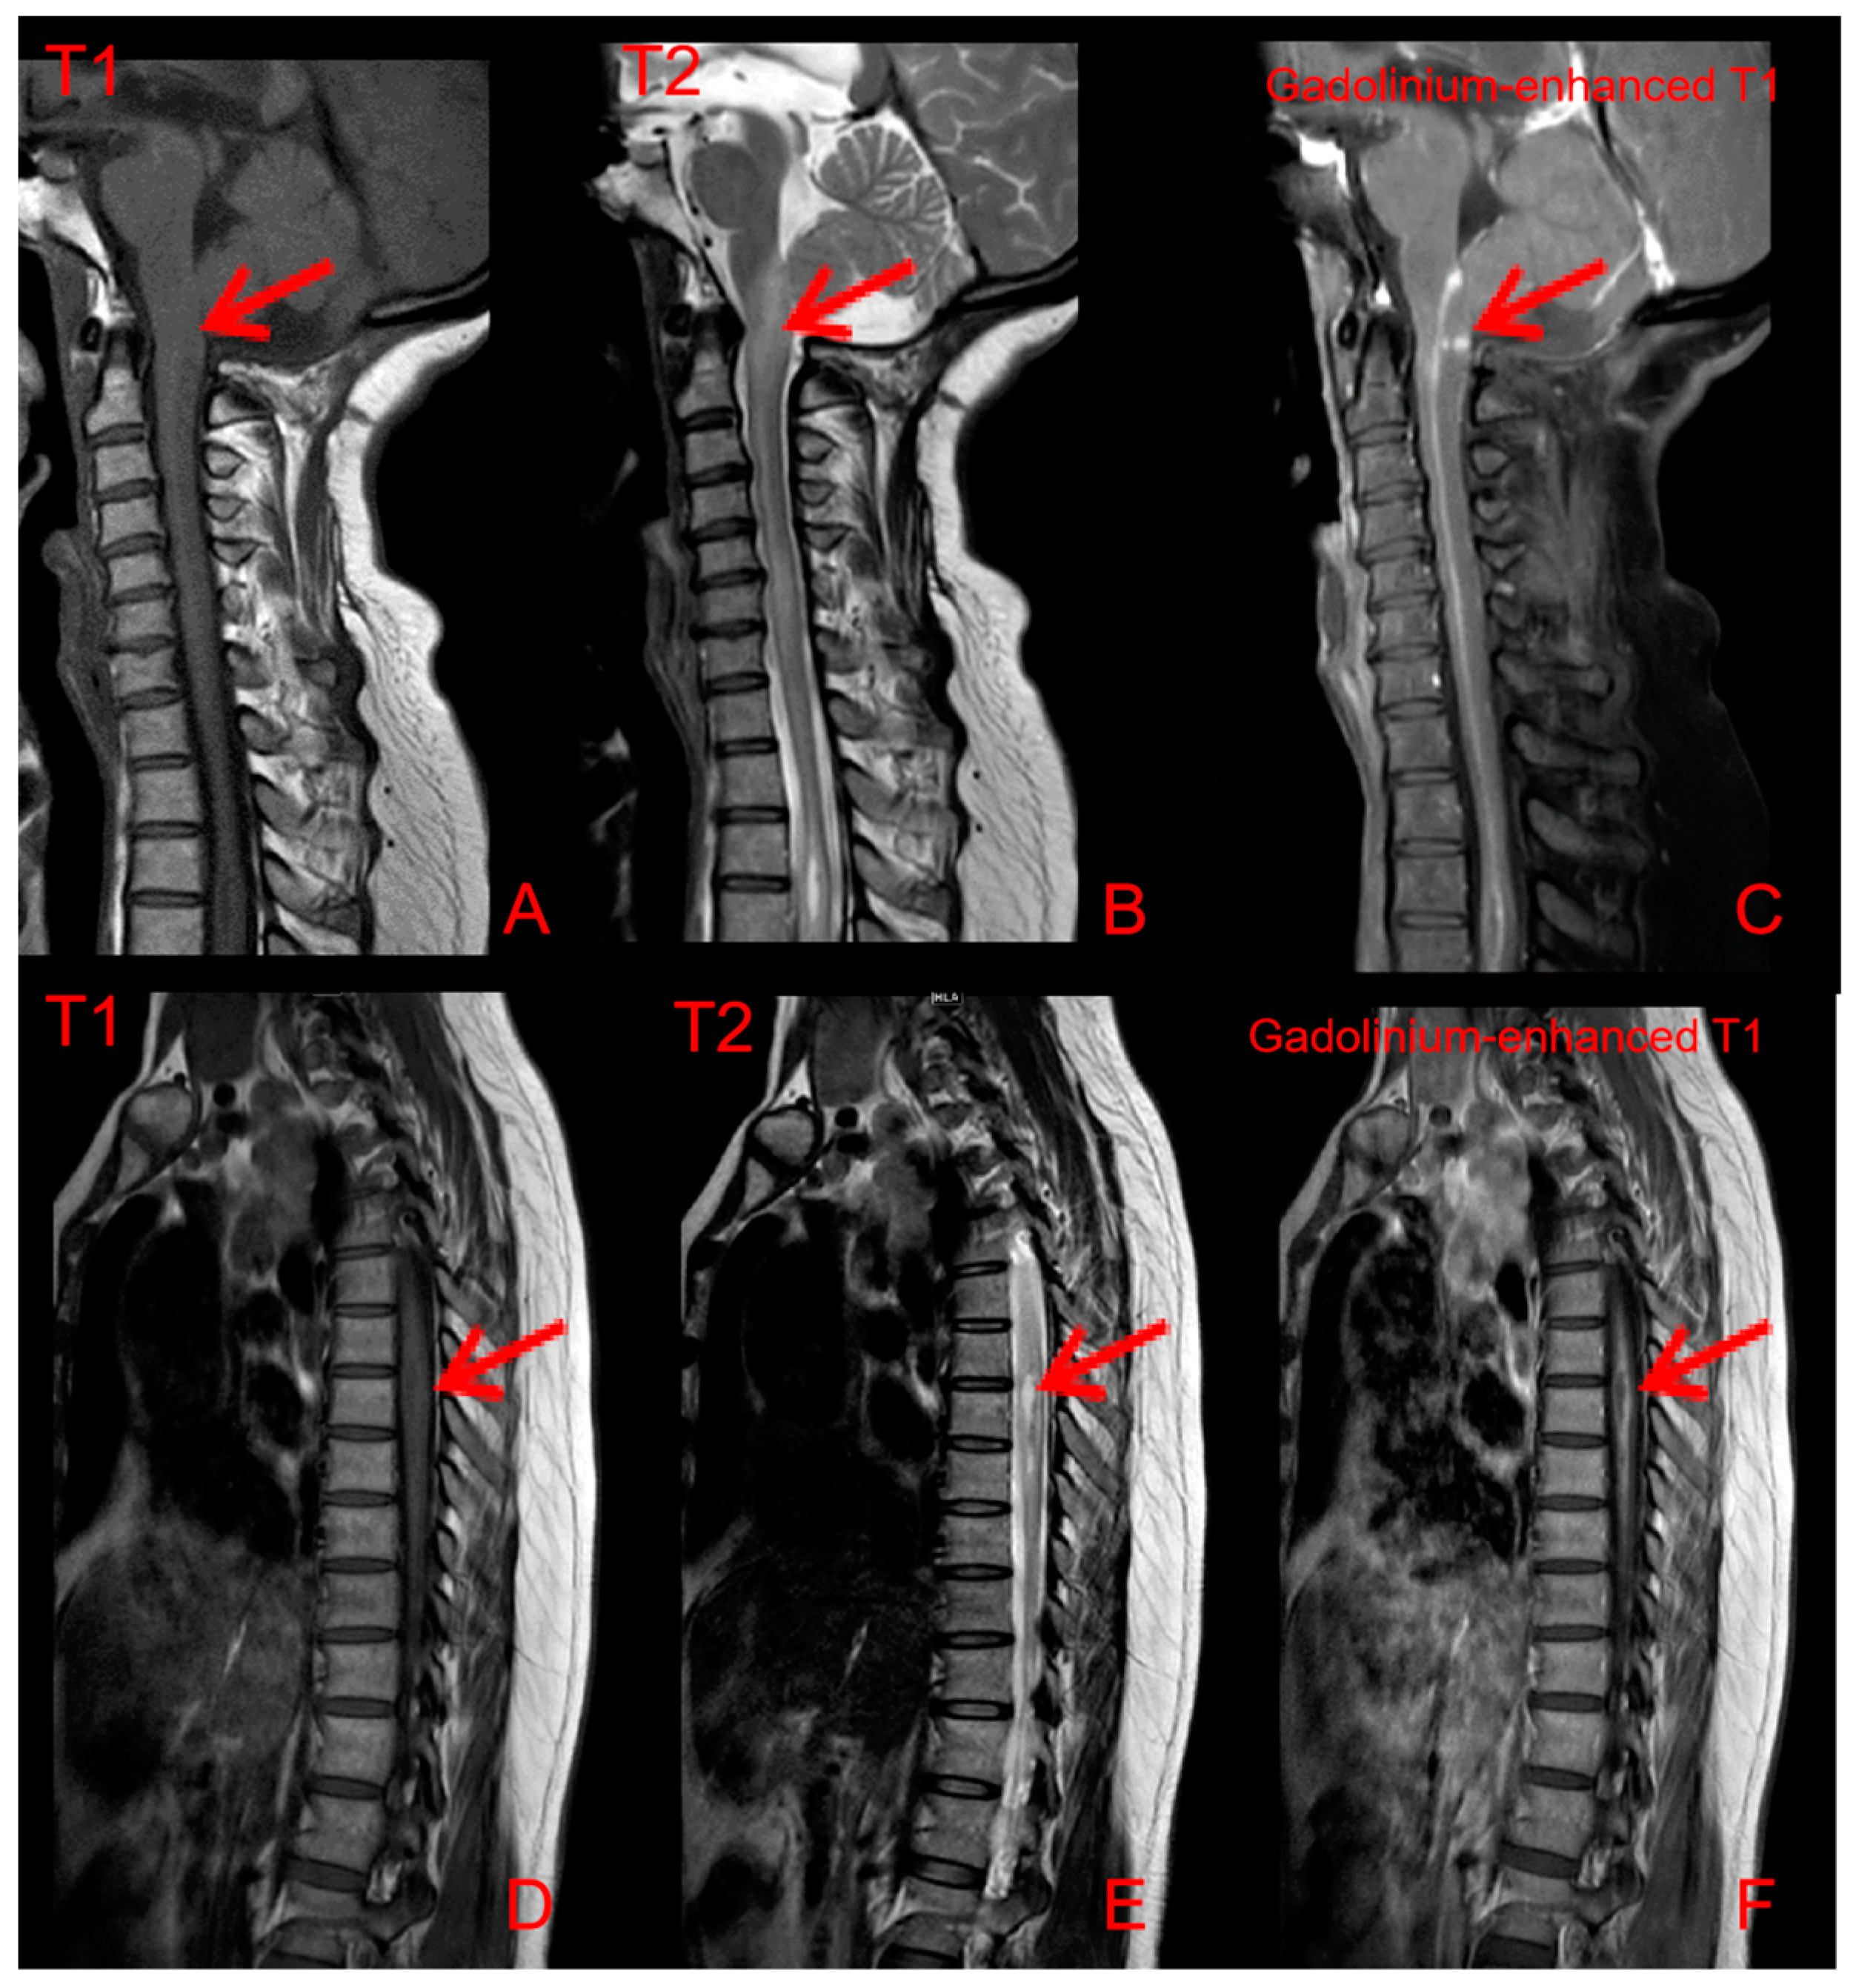

2. Case Presentation